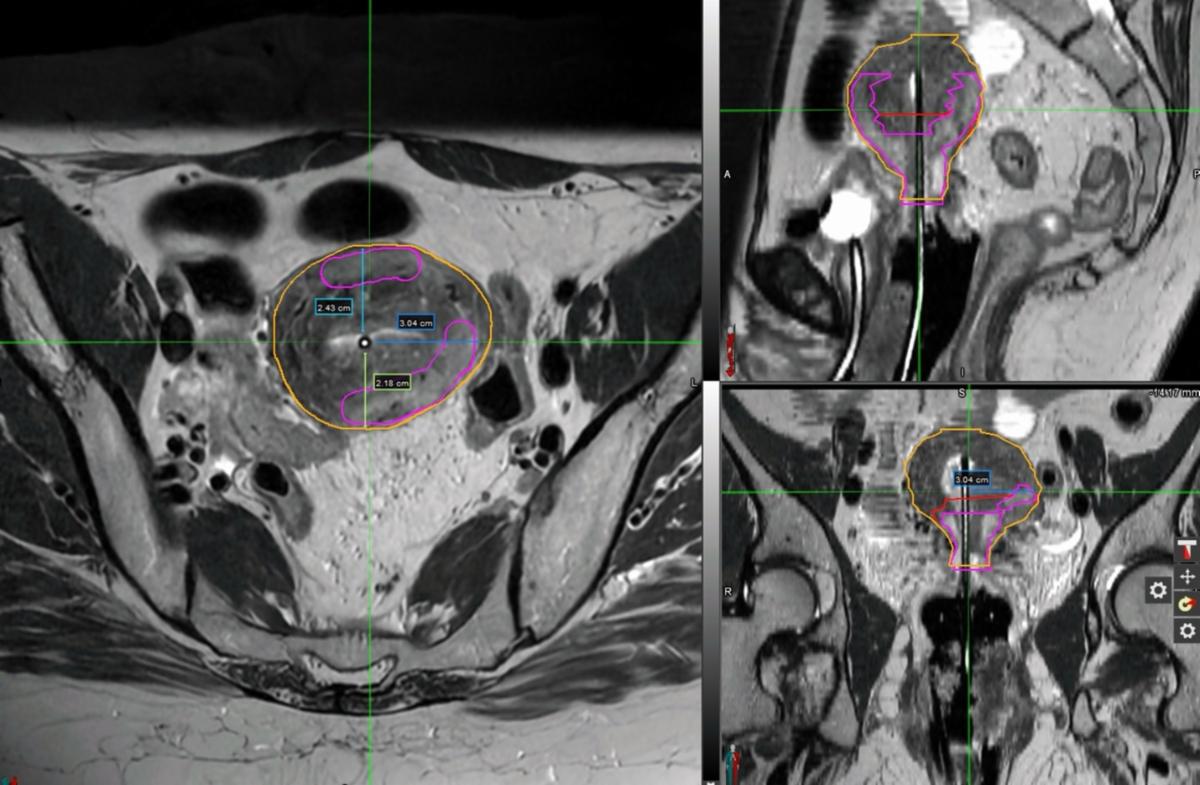

Given the extent of disease, she was recommended and ultimately treated with definitive external-beam radiotherapy (EBRT) and concurrent weekly cisplatin (40 mg/m2 IV) followed by four fractions of high-dose-rate (HDR) cervical brachytherapy. EBRT was delivered to the pelvis and at regional nodes to 45 Gy, followed by HDR brachytherapy, 4 fractions of 7 Gy each to the cervical high-risk clinical tumor volume (HR-CTV), delivered twice-weekly. Serial exams during EBRT showed early response. Repeat pelvic MRI in week 4 confirmed tumor response but with residual disease (Figure 2).

At the time of first brachytherapy, exam under anesthesia demonstrated an irregular cervix without gross exophytic disease. After sounding to 7 cm, a 15-degree MRI/CT-compatible uterine tandem (Elekta, Geneva) was placed under ultrasound guidance with 25 mm semilunar ovoids/colpostats were selected. In anticipating needing to cover disease beyond tandem and ovoids, six interstitial catheters were pre-loaded into the guide tubes which were then attached to the appropriate positions in the ovoids. The ovoids/colpostats/guide tubes/interstitial catheters were advanced into the vaginal fornices, and the colopostats were secured to the tandem to achieve appropriate geometry. A rectal paddle was placed under the ovoids. A locking mechanism was placed. Patient was then imaged with CT in the brachytherapy suite to appropriately advance interstitial catheters in desired positions. Three (2 medial and 1 left lateral posterior) interstitial catheters were advanced 4-5 cm depending on their position. Following confirmation of placement with repeat CT, patient was transferred to MRI scanner where images were obtained, confirming appropriate positioning of the applicators and packing (Figure 3A).

MRI images were then used for brachytherapy planning, and were fused to her CT to assist with catheter reconstruction. The uterus measured approximately 6-6.5 cm left-to-right, with the tandem centered in the uterine cavity (Figures 3B-E). Given this, tandem was likely not going to adequately cover the entirety of residual GTV in the myometrium without excessive hotspots. An individualized plan delivering 7 Gy per fraction was optimized to balance target coverage and normal-tissue sparing, using four channels (tandem x1, ovoids x2, and interstitial needle x1). The rest of the interstitial catheters were not used as they did not improve the plan. Some of the tandem dwell positions were loaded 92 to 130.5 seconds, extending lateral coverage with doses up to 187% of prescription dose (13 Gy). Reasonable coverage was achieved with 91.5% HR-CTV V90% (Table 1).

Figure 2 – mid-treatment Pelvic MRI, T2 sequence

Figure 3A: HDR-BT Fraction 1 MRI

Figure 3B-E: HDR-BT Fraction 1 MRI in MIM treatment-planning software